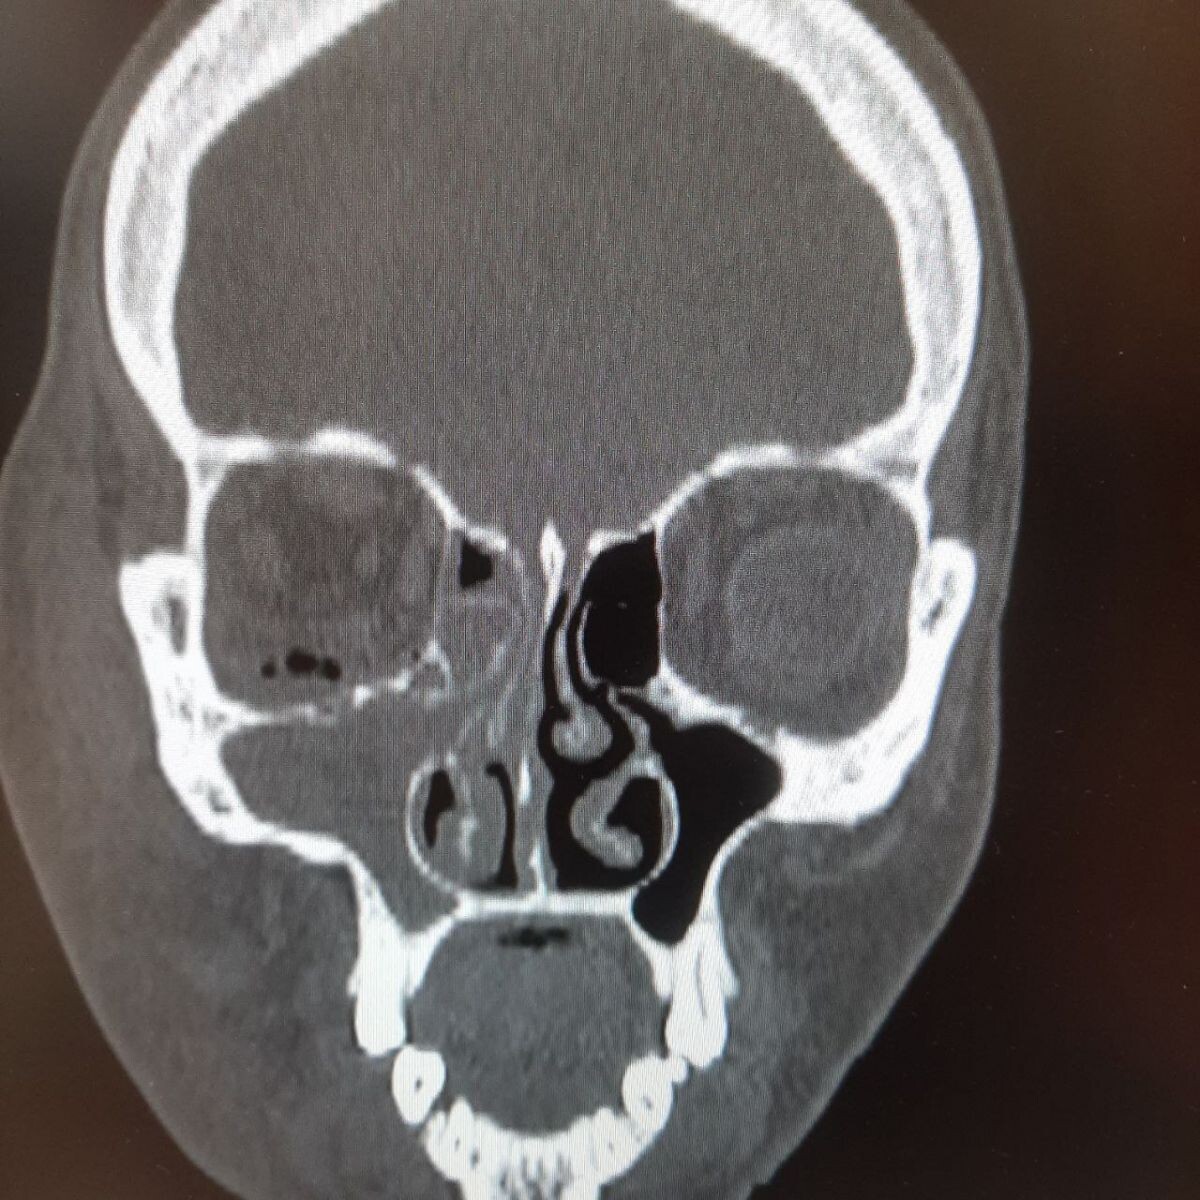

Непролеченные зубы могли привести к гибели орловчанки. Подробности спасения женщины рассказали в областной больнице. Врачам пришлось спасать пациентку с флегмоной. К моменту поступления в больницу в глазнице уже образовался газ. Также женщина уже страдала гнойным гайморитом. Оказалось, что развитию флегмоны предшествовало хроническое воспаление верхнечелюстной пазухи на фоне непролеченных зубов. Причем орловчанка почти две недели пытались лечиться самостоятельно. В итоге медики ООКБ вскрыли флегмону и удалили зубы, из-за которых она развилась. Женщине пришлось четыре дня провести в реанимации.

Врачам пришлось спасать пациентку с флегмоной. К моменту поступления в больницу в глазнице уже образовался газ. Также женщина уже страдала гнойным гайморитом.

Оказалось, что развитию флегмоны предшествовало хроническое воспаление верхнечелюстной пазухи на фоне непролеченных зубов. Причем орловчанка почти две недели пытались лечиться самостоятельно.